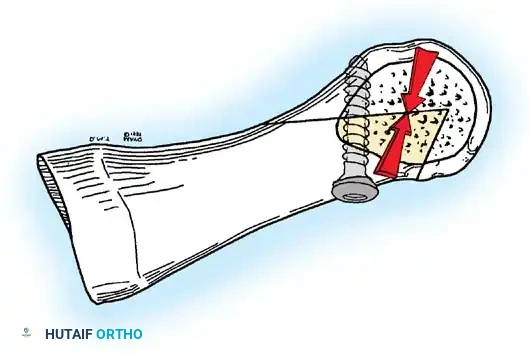

The following modifi cations of the Keller technique can expand the indications for use with more severe deformities.

REMOVAL OF THE FIBULAR SESAMOID

• When the medial eminence and phalangeal base have been excised, remove the fi bular sesamoid.

• Place a sturdy two-toothed retractor beneath the metatarsal head, and have an assistant lift it dorsally.

• Using a Freer elevator or a small osteotome for its strength, mobilize the fi bular sesamoid (Fig. 78-31A to C). This may be diffi cult in elderly patients with signifi cant deformity and adherence of the sesamoid to the metatarsal head. Lift the metatarsal dorsally for exposure (Fig. 78-31D and E).

• When the sesamoid is mobile, identify the fl exor hallucis longus tendon by placing traction on the hallux and fl exing and extending the interphalangeal joint of the hallux. The tendon is visible just distal to and in alignment with the sesamoids, which straddle it.

• Identify and expose the lateral neurovascular bundle just lateral to the tendon by blunt dissection.

• Pull the plantar medial capsule medially. This requires a fi rm grasp on the capsule. The medial traction brings the intersesamoid “ligament” into better view.

• Incise the intersesamoid ligament longitudinally with a No. 67 Beaver or No. 15 Bard-Parker blade. If tenotomy scissors are used, place one arm of the scissors under the ligament (this arm rests on the dorsal side of the fl exor hallucis longus) and the other arm dorsal to the ligament.

• When the intersesamoid ligament is incised, grasp the sesamoid fi rmly with forceps or a small Kocher clamp, fl ex the toe at the interphalangeal and metatarsophalangeal joints to relax the fl exor hallucis longus tendon, and pull the fi bular sesamoid distally and medially.

• With release of the intersesamoid ligament, the medial surface of the fi bular sesamoid is free from soft tissue. Distally, the sesamoid is free because of resection of the base of the proximal phalanx. This leaves two sides of the sesamoid, distal and medial, free of soft tissue.

• While pulling the sesamoid distally and medially, use a small blade to incise along the lateral margin of the sesamoid under direct vision. Keep pulling the head of the metatarsal dorsally and holding the hallux distracted and in fl exion. This greatly aids in identifi cation of the margins of the fi bular sesamoid, particularly laterally and proximally.

• The most diffi cult part of the sesamoidectomy and that which should be done last is release of the proximal lateral corner of the sesamoid where the fl exor hallucis brevis lateral head inserts. While incising the lateral capsular attachments to the sesamoid, do not bury the blade of the knife because the neurovascular bundle to the lateral side of the hallux is just lateral to the capsule.

• Now all attachments to the fi bular sesamoid have been removed except the lateral head of the fl exor hallucis brevis, which inserts on the proximal lateral margin of the sesamoid. This is a diffi cult section to remove; however, this section can be released under direct vision by pulling the sesamoid distally and medially and lifting the metatarsal head dorsally with a strong two-toothed retractor.

• When the sesamoid has been removed, insert two 0.062-inch Kirschner wires retrograde from the tip of the toe 2 to 3 mm plantar to the nail bed, leaving about 5 to 7 mm of the pins exposed at the base of the phalangeal remnant to help align the phalanx on the metatarsal before antegrade passage of the pins into the metatarsal (Fig. 78-31F).

LATERAL DISPLACEMENT OF THE FIRST METATARSAL

• Push the metatarsal laterally several times. Occasionally, this does not move the metatarsal, but some lateral mobility usually is present.

Fig. 78-31 Excision of fi bular sesamoid in modifi ed Keller procedure. With base of proximal phalanx removed and medial eminence excision, exposure of fi bular sesamoid is not as diffi cult from medial incision. A, Operative photograph showing elevation of fi rst metatarsal with strong two-tooth retractor and use of small osteotome to mobilize fi bular sesamoid and lateral capsuloligamentous (frequently contracted) structures. Osteotome is between metatarsal head and lateral sesamoid. When mobilization of fi bular sesamoid is complete, entire sesamoid is visible for excision. Note chondromalacia of tibial sesamoid articular surface medial to osteotome. B, Fibular sesamoid has been excised, and lateral capsular structures and conjoined tendon (in forceps) have been released. Neurovascular bundle to lateral side of hallux is adjacent to these structures. C, Diagrammatic representation of modifi ed Keller procedure. By excising fi bular sesamoid, valgus moment of conjoined tendon of fl exor hallucis brevis and adductor hallucis no longer pulls fl exor hallucis longus tendon laterally (carrying hallux with it) through capsulosesamoid plantar plate and pulley system. D, Metatarsal head must be lifted dorsally to excise fi bular sesamoid under direct vision. E, Note exposure of fi bular sesamoid after mobilization of metatarsal head. Continued